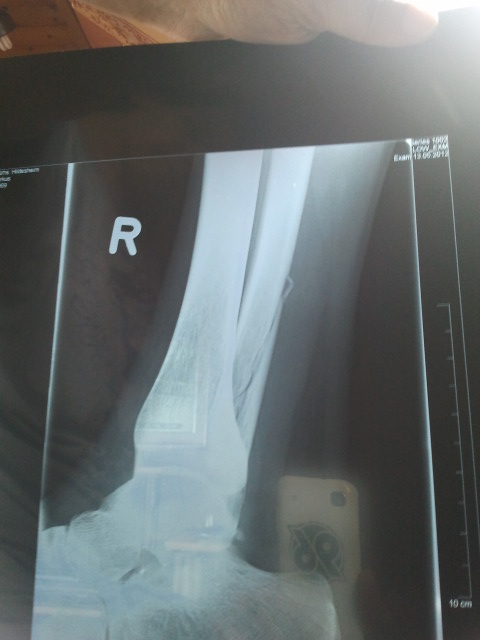

Der Bruch am 13.05.2012

Nach der Op am 20.05.2012